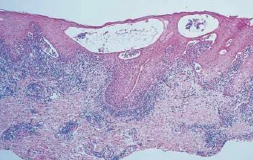

上皮裂解

Acantholytic Disorder

Pemphigus

天疱瘡

自體免疫疾病

vulgaris (PV,常見) Ab 打 Desmosomes 50y

• 不結疤,眼球不沾黏

• 口腔病變 first come, last go

• Desmoglein 3: 口內

• Desmoglein 1: 皮膚表層

• 大水泡,薄水泡,破水泡

• Nikolsky sign

• row of tombstones: 只剩 Basal cell 像 Cleft 突出去

• acantholysis → Tzanck cell (飄落在Celft 中)

• 上皮細胞之間沉積抗體(IgG, IgM)和補體(C3)

• 濃度與臨床症狀嚴重度相關